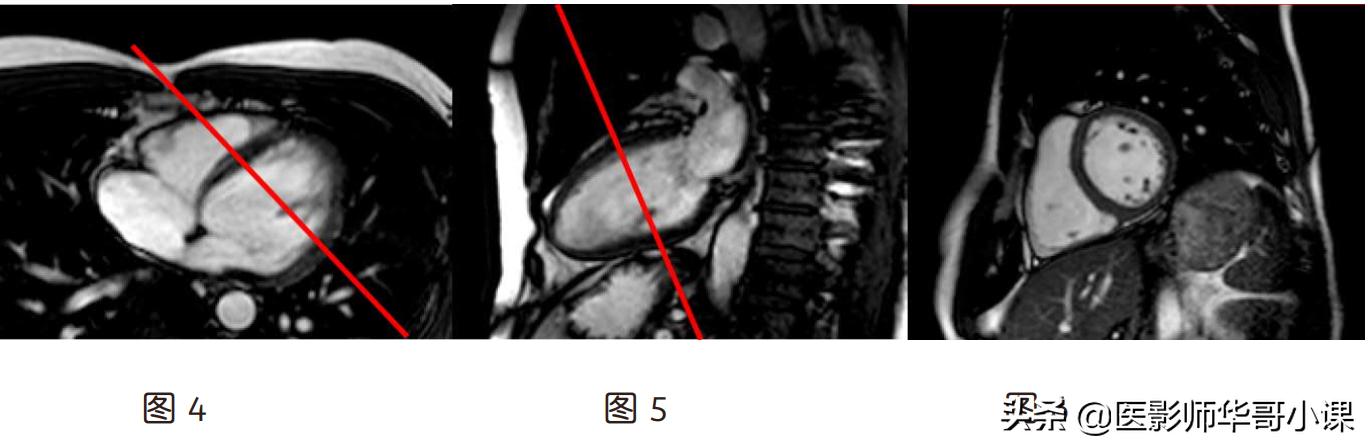

(2)短轴位(图 6):横轴位上(图 4)定位线垂直室间隔,假左两腔心(图 5)上定位像

垂直心尖到二尖瓣口中点